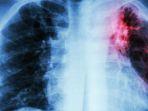

TBC ialah penyakit yang menyerang paru-paru dan penyebarannya sulit diberantas. Penyakit ini mudah menyebar dengan airborne infection atau udara.

Penyakit TBC sangat menular dengan airborne infection dengan kata lain penularan bisa melalui udara. Penyakit ini termasuk sulit untuk diberantas.